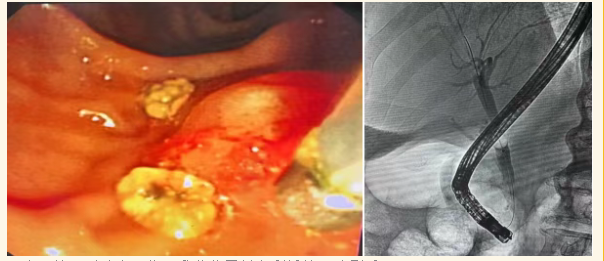

手术过程:Step 1(Day 1)ERCP胆总管取石术经口十二指肠镜精准取石,创伤小、恢复快,短期可实施二次手术,规避胆管切开取石感染风险。

(十二镜下到达十二指肠乳头位置并顺利插管及造影后取石)